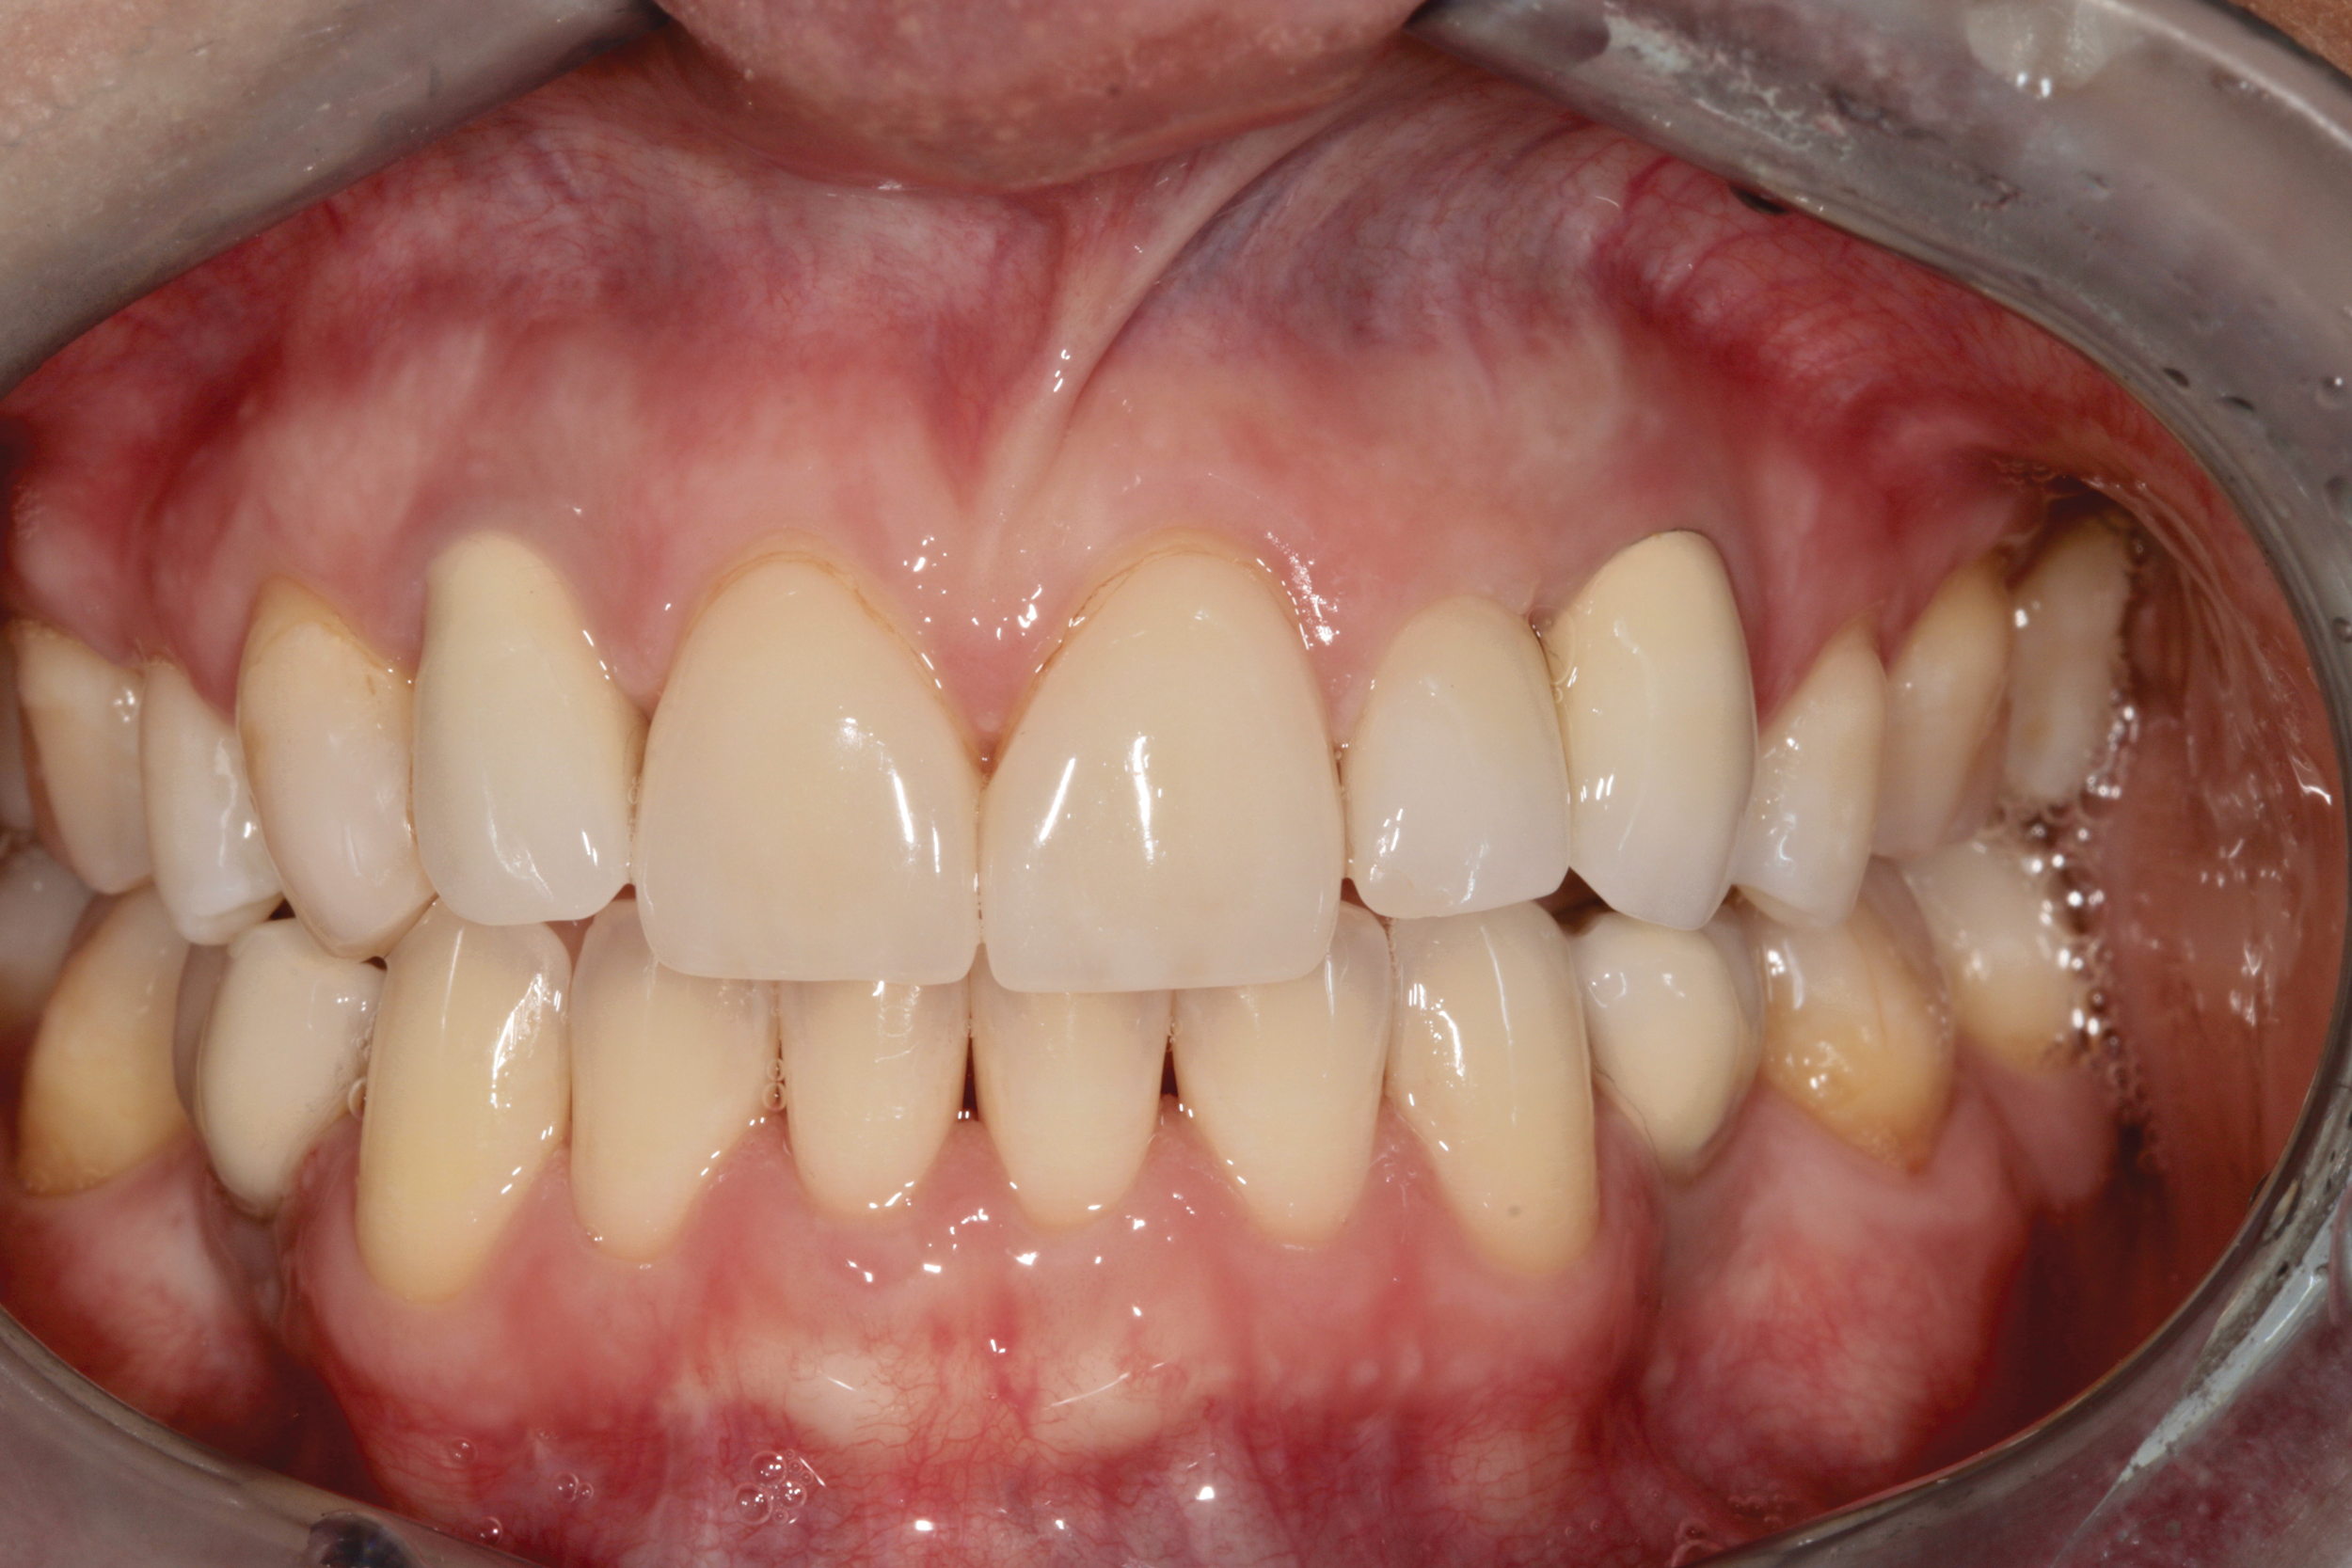

Canine substitution can be an excellent alternative for the replacement of the missing maxillary lateral incisor (Figure 1 and Figure 2). This treatment option can be particularly effective if the canine has a flat facial surface, is not too wide mesiodistally, and has a color similar to the contralateral lateral incisor. Patients with missing lateral incisors who present with maxillary dentoalveolar protrusion and/or an Angle class II molar relationship and minimal crowding in the mandibular arch are considered excellent candidates for canine substitution.7

Fig 1. Patient was missing teeth Nos. 7 and 10 (Fig 1). Canine substitution was the treatment used to replace these missing teeth (Fig 2).

Fig 2. Patient was missing teeth Nos. 7 and 10 (Fig 1). Canine substitution was the treatment used to replace these missing teeth (Fig 2).